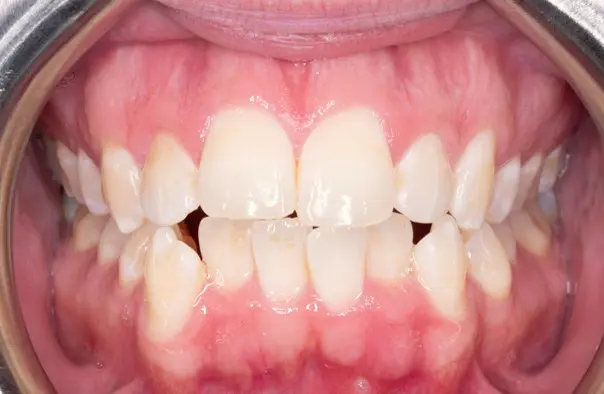

Crossbite

Before

After